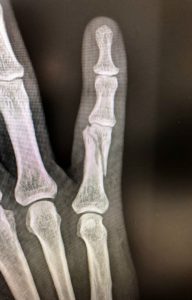

Figura 2 - Fractura falange 5º dedo desplazada. (Ver también Figura 6)

Figura 6 - Osteosíntesis con tornillos de Fractura falange 5º dedo desplazada.